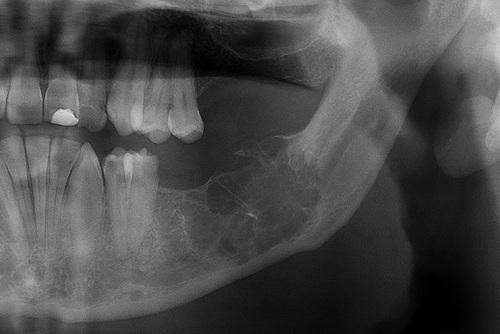

A cyst is located in the third molar area in a patient with no history of third molar extraction. The cyst was excised, and histopathologic examination revealed an odontogenic keratocyst (OKC).

primordial cyst